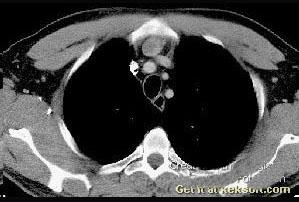

问题 女,45岁,抑郁嗜睡1个月,实验室检查血钙3mml/L,CT图像如图,最可能的诊断为 ( )

选项 A.正常 B.用存上腔静脉干 C.胸内甲状旁腺瘤 D.胸内甲状腺瘤 E.囊性胸腺瘤

答案 C